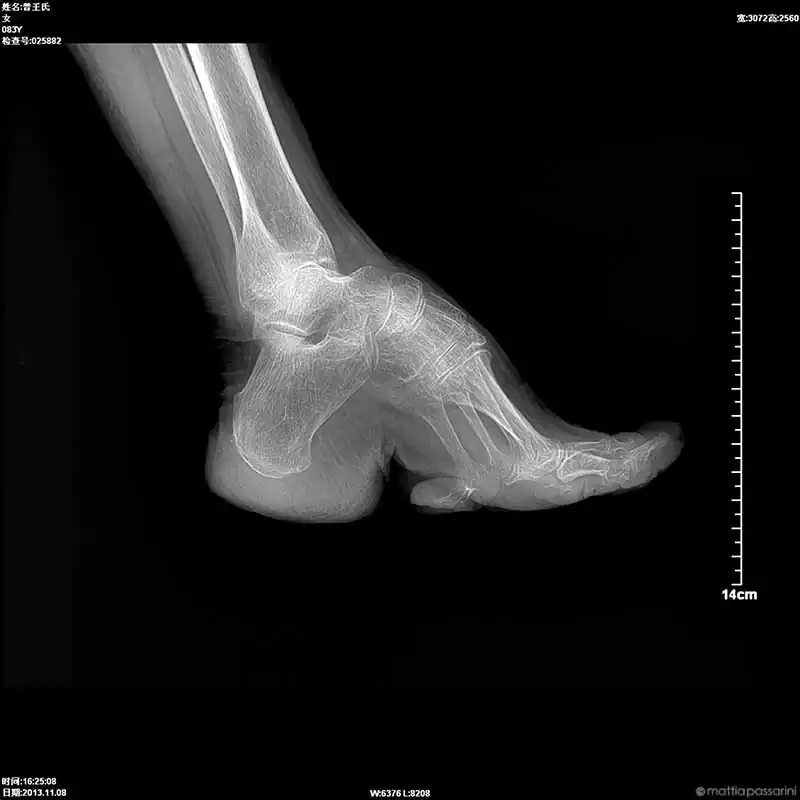

Foot binding became popular as a means of displaying status (women from wealthy families who did not need them to work could afford to have their feet bound) and was correspondingly adopted as a symbol of beauty in Chinese culture and was also a prerequisite for finding a rich husband for poorer women. The process was started before the arch of the foot had a chance to develop fully usually between the ages of 2 and 5. First, each foot would be soaked in a warm mixture of herbs and animal blood, this was intended to soften the foot and aid the binding. Then, the toenails were cut back as far as possible to prevent in-growth and subsequent infections, since the toes were to be pressed tightly into the sole of the foot. To enable the size of the feet to be reduced, the toes on each foot were curled under, then pressed with great force downwards and squeezed into the sole of the foot until the toes broke. When unbound, the broken feet were also kneaded to soften them and the soles of the girl’s feet were often beaten to make the joints and broken bones more flexible. All the process to have a final nice looking binding foot took almost two years. An attribute of a woman with bound feet was the limitation of her mobility, and therefore, her inability to take part in politics, social life and the world. Bound feet rendered women dependent on their men, and became an alluring symbol of chastity and male ownership. In 1912, the new government of China banned foot binding. Since the beginning of this practice over 300 million women have had the foot bound, now just few elderly Chinese women still survive today. [Official Website]